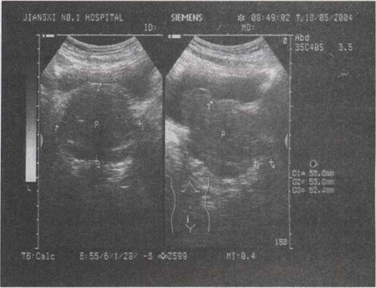

49.男,65岁,排尿困难,尿线细,滴淋,尿后不尽感等临床症状,超声如图所示,最可能的诊断为()